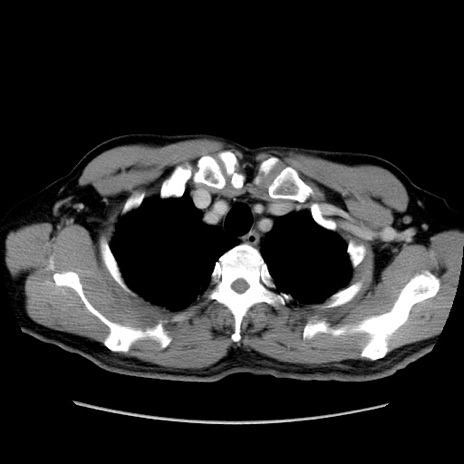

症例34(横断像)

【症例】60歳代 男性

冠状断像

矢状断像